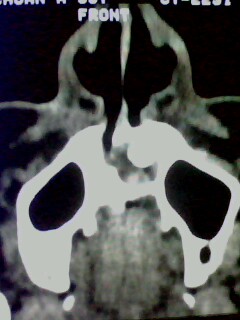

以下是引用随光逐影在2009-5-20 19:22:00的发言:[br]1)考虑左上颌骨近中线区含牙囊肿。2)鼻中隔右突偏曲。3)双侧下鼻甲肥大。